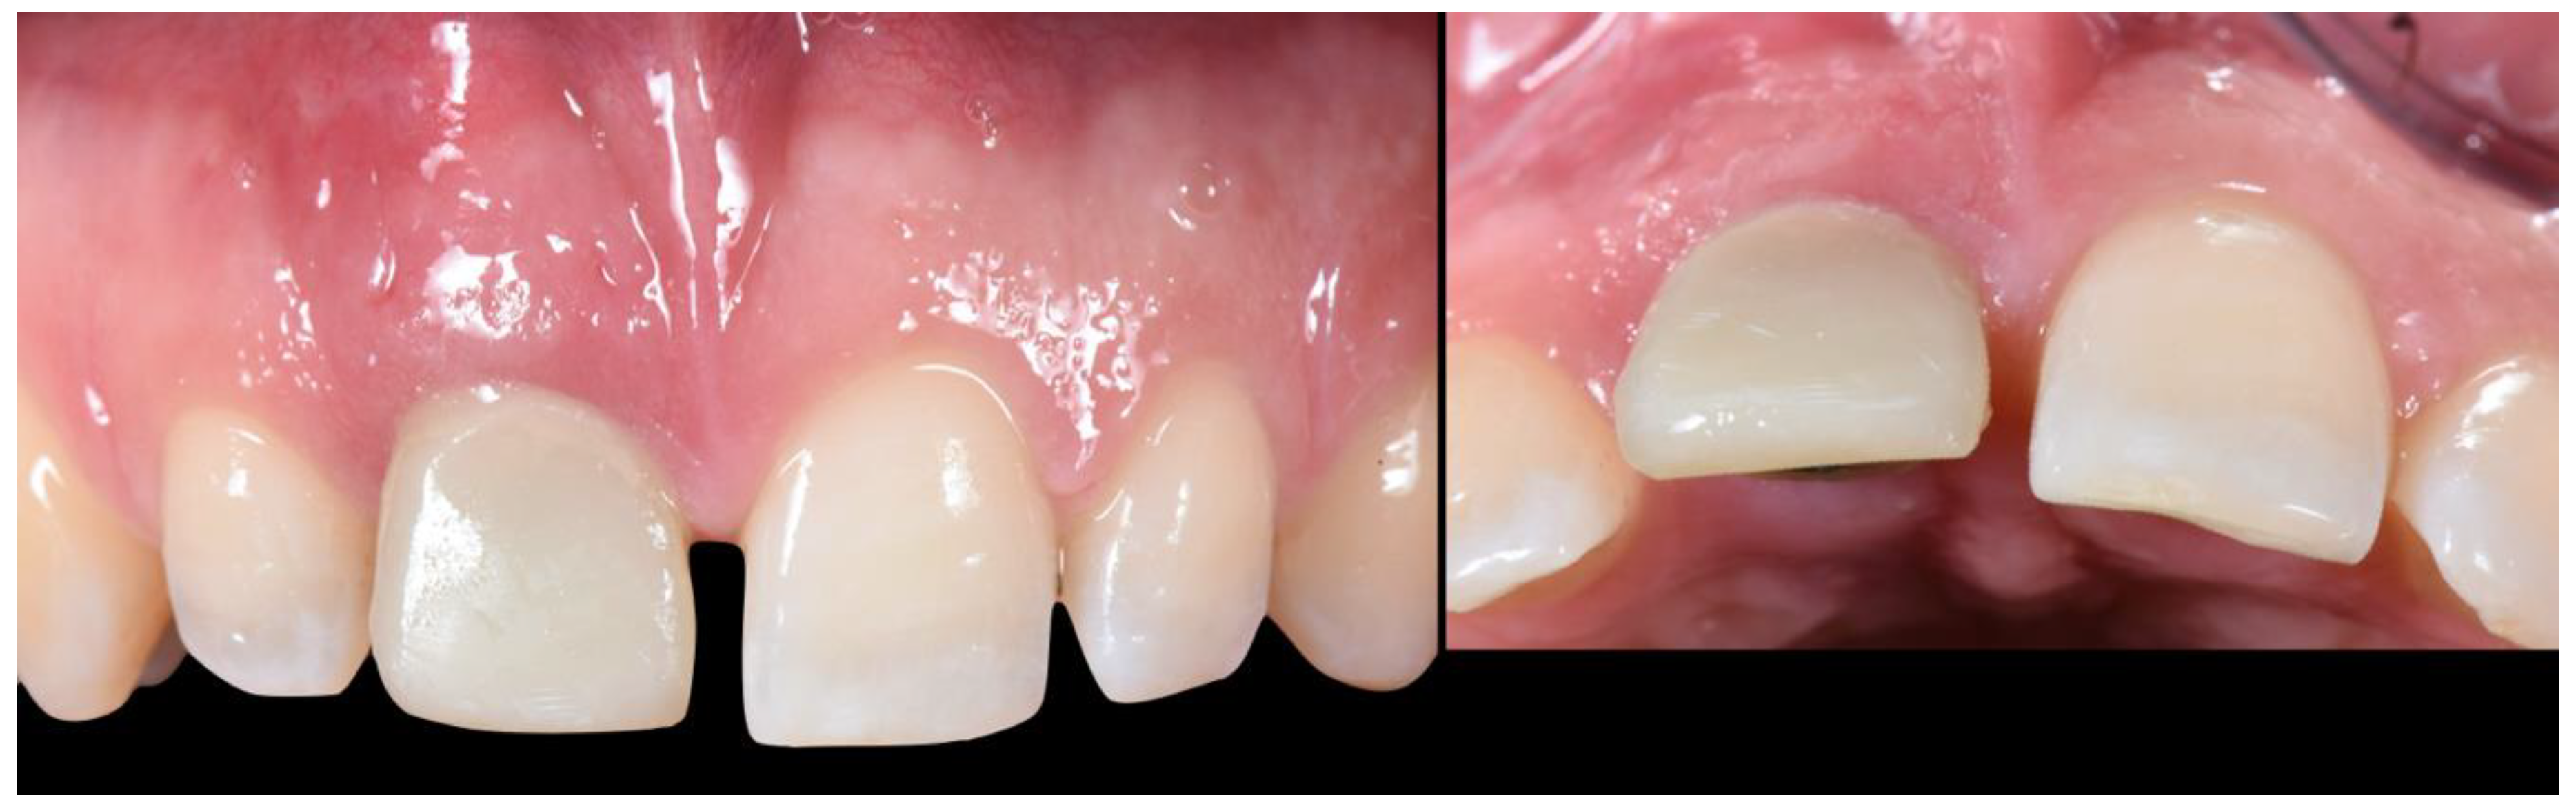

2.4. Transitional Restoration Stage

2.5. Impression Stage